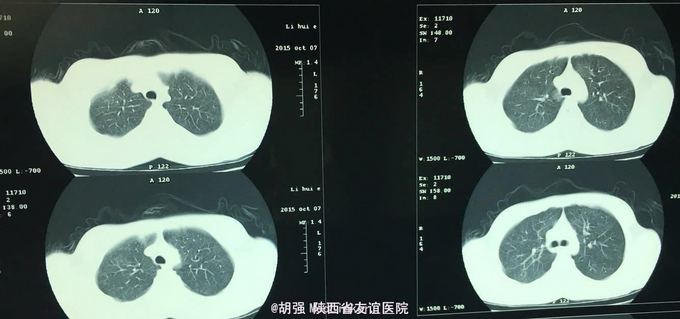

查体:口唇无发绀,咽充血,双侧扁桃体2度大,表面可见脓胎。两肺呼吸音粗糙,可闻及管状呼吸音。余查体无明显异常。 辅助检查:血常规提示白细胞及血小板明显低于正常值,肝功提示转氨酶升高。凝血系列:PT、APTT时间明显延长。T sport试验弱阳性。10月份胸部CT平扫未见明显异常。10月26日及12月12日胸片未见明显异常。12月19日胸部CT提示:两肺斑片状阴影,两侧胸腔积液。